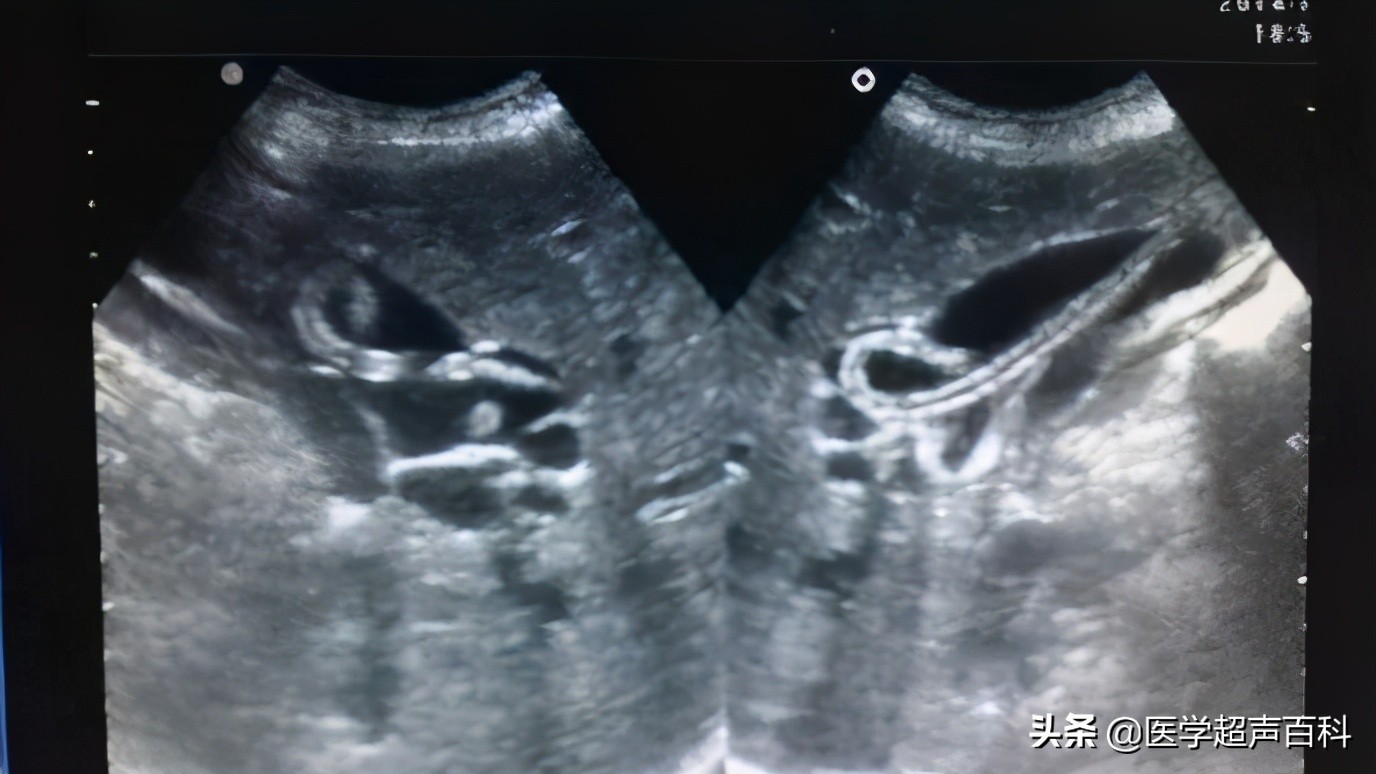

3.有多条蛔虫胆管内可见多条双线状平行高回声带,如几十条蛔虫绞成团,堵塞胆管时见到胆管有极度扩张。

5.肝内胆道蛔虫,可见肝内胆道明显扩张,及其中平行双线状高回声带。存活蛔虫可见蠕动。

6.胆囊蛔虫病,在胆囊内呈现双线状高回声平行光带,多呈弧形或蜷曲状。